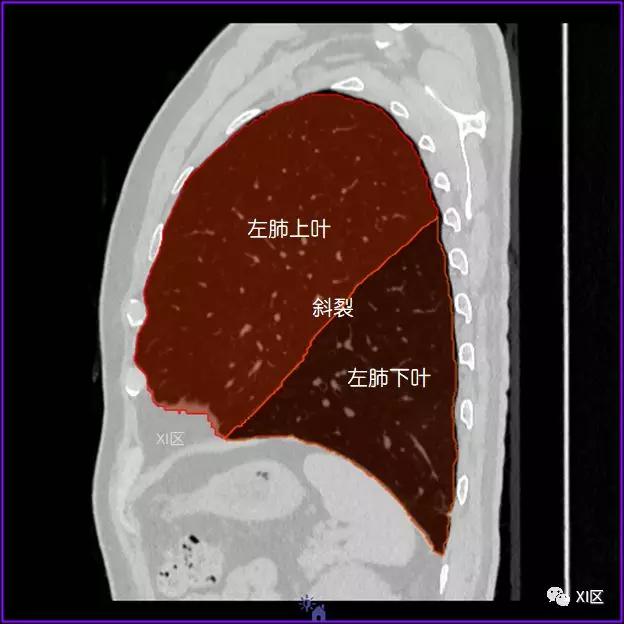

肺的分叶

左肺借斜裂成上、下两叶;右肺借斜裂和水平裂成上、中和下叶三叶。

矢状位